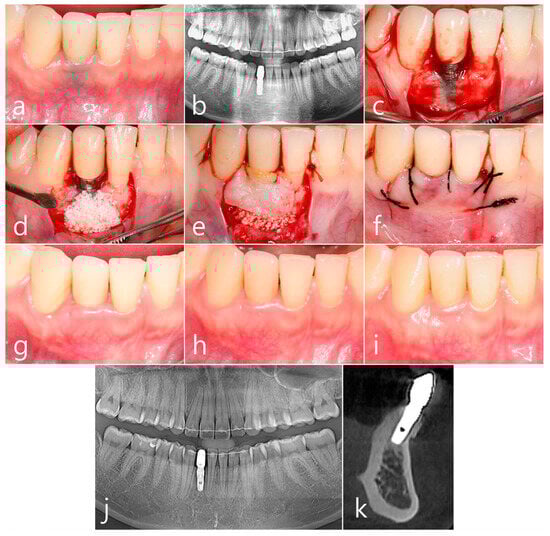

2.2. Case 2